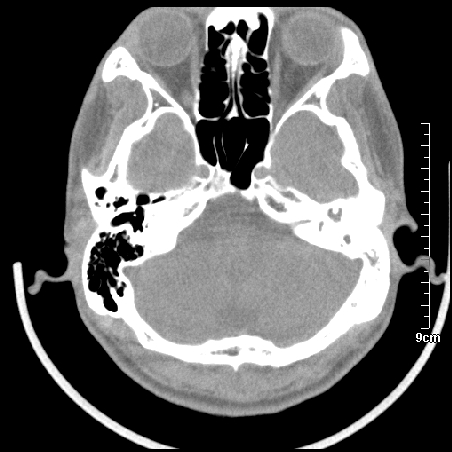

病例1

m/46y 头晕.耳鸣半月余 有乳突炎病史

病例2

m/27

胆脂瘤是是以鳞状上皮内衬充满角质化碎片的囊,随着角化屑片的不断堆积,肿块逐渐增大,胆脂瘤可为先天性(2%)或后天性(98%)。胆脂瘤有感染史。中耳内的鳞状上皮通常有外耳道的上皮通过一鼓膜的缺损移行至中耳,其他的原因包括鳞状上皮化生。由于欧氏管的功能不全所引起的中耳负压可产生上鼓室鼓膜松弛部的牵引性开袋。继而发展成胆脂瘤。成年人胆脂瘤时乳突常发育差,而儿童常有广泛性乳突气化,这种气化可导致胆脂瘤的更广泛的乳突扩散。后天性胆脂瘤患者大多数存在骨质破坏。

松弛部胆脂瘤有中央性穿孔或后上部牵引口袋所致。紧张部胆脂瘤经常侵蚀听小骨并引起传导性耳聋。

中耳胆脂瘤有两个重要并发症:一是面神经管的水平段受暴露,二是外侧半规管受侵蚀产生瘘管。面神经在ct上难以显示或不可能显示,除非其周围有空气包绕或有良好轮廓的骨性覆盖。胆脂瘤还可合并感染,产生于急性中耳炎.乳突炎所描述的那些合并症。